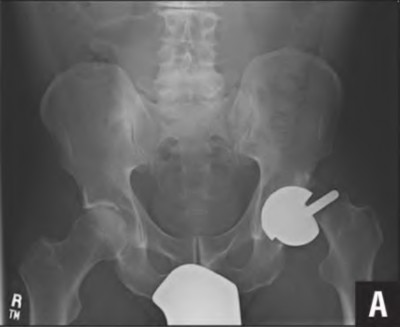

An 82-year-old woman falls and sustains the fracture shown in figure A. She denies any history of dislocation or prodromal pain prior to her fall. What is the most appropriate treatment?

The radiograph demonstrates a periprosthetic femur fracture extending to the tip of the stem. The long spiral fracture is consistent with a loose implant. The bone stock is sufficient. Therefore, this fracture pattern would classify as a B2 using the Vancouver classification system. The Vancouver classification for periprosthetic femoral fractures is simple yet incorporates all the pertinent factors such a location, stem fixation, and bone stock. Type A is a trochanteric fracture- lesser or greater. These can be treated non-operatively usually and ORIF if symptomatic. Type B fractures are around or just below the stem and are subdivided into three types. Type B1 is a fracture with a well fixed stem.

The treatment is cable plating or allograft struts or a combination of the two. Type B2 is a fracture with a loose stem with good bone stock. The treatment is a cementless porous coated long stem atleast two diameter length past the

fracture site. Type B3 is a fracture with a loose stem and comminution. For younger patients, use cementless porous coated long stems with allograft struts. For older patients, consider a tumor prosthesis. Cement fixation is sometimes necessary Type C is a fracture well below the stem tip. These can be treated independently of the prosthesis.

Springer et al showed optimal outcomes with revision involving long extensively-coated femoral stems for Vancouver B fractures.

Masri et al review the classification and treatment of periprosthetic femur fractures.

Figure A shows a lytic lesion of the proximal femur with an intramedullary implant. Figure B shows a proximal femoral replacement.